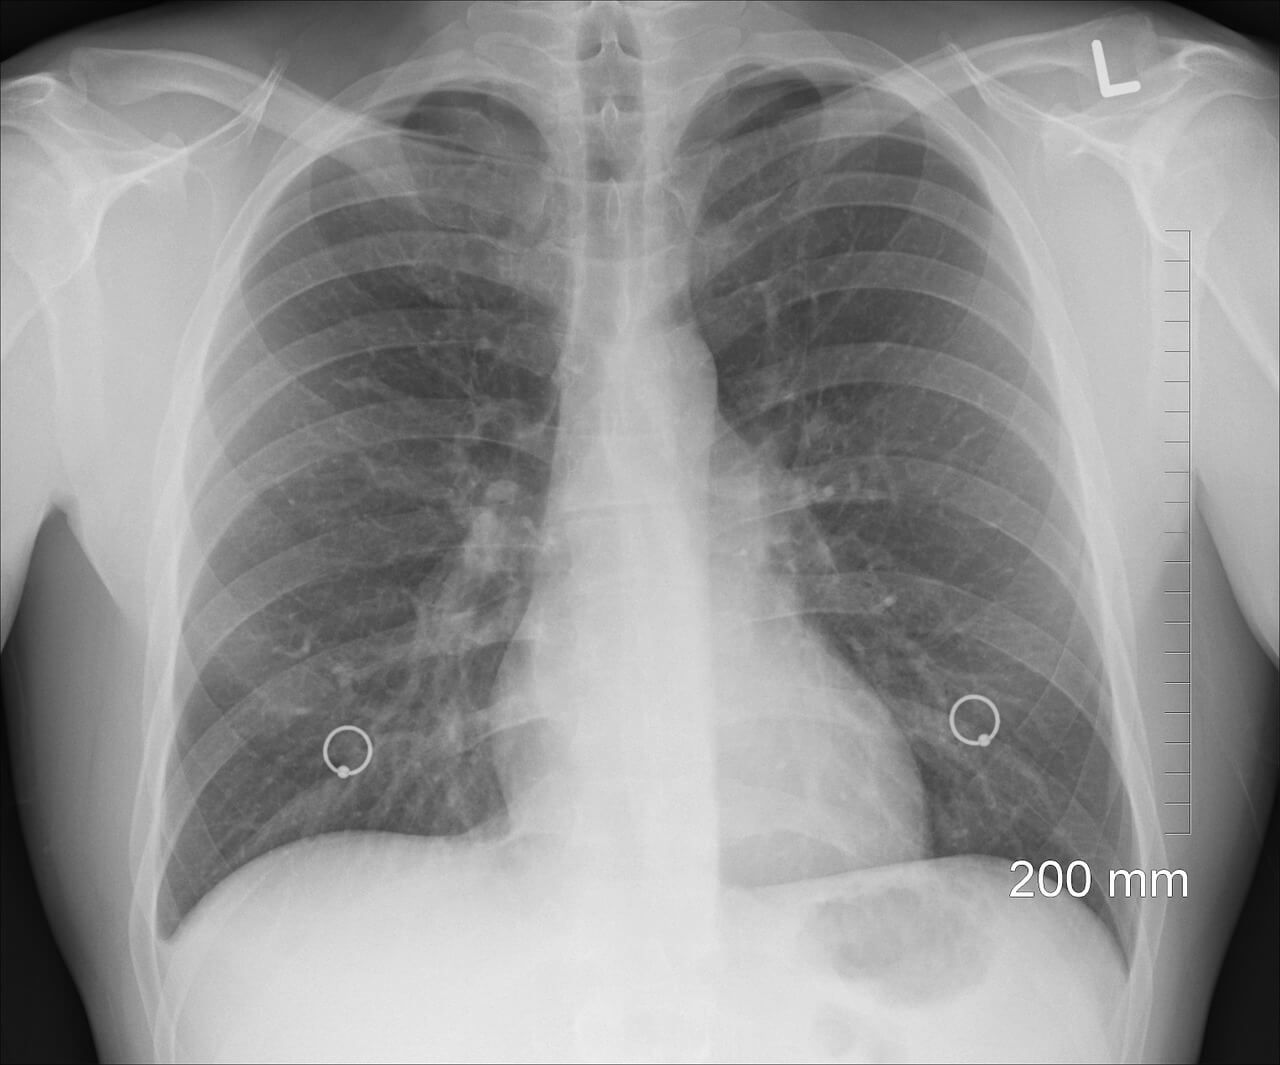

Врач рассказала, почему при вентиляции легких есть риск бактериальной пневмонии

К бактериальной пневмонии может привести процедура кислородотерапии, которая может использоваться при лечении COVID-19, – так считает научная сотрудница исследовательского института дезинфектологии Роспотребнадзора, член-корреспондент РАН Елена Иванова.

По её словам, подача кислорода, искусственная и принудительная вентиляция легких могут привести к тому,что в нижние дыхательные пути человека могут попасть бактерии и флора из верхних путей. Врач напомнила, что больше всего микробов у человека во рту и в носу, но пойти ниже им не даёт слизистая оболочка, которая становится барьером, берет на себя возможные бактериальные опасности. Но иная ситуация, по словам эксперта, происходит при принудительной вентиляции легких и кислородной терапии:

Это и может в итоге вызвать бактериальную пневмонию. Отмечается, что большинство бактерий, которые могут поразить легкие произошли от своих почвенных предков, что обеспечивает им высокую живучесть. Они распространены в местах общего пользования, встречаются в туалетах, обитают на предметах гигиены.